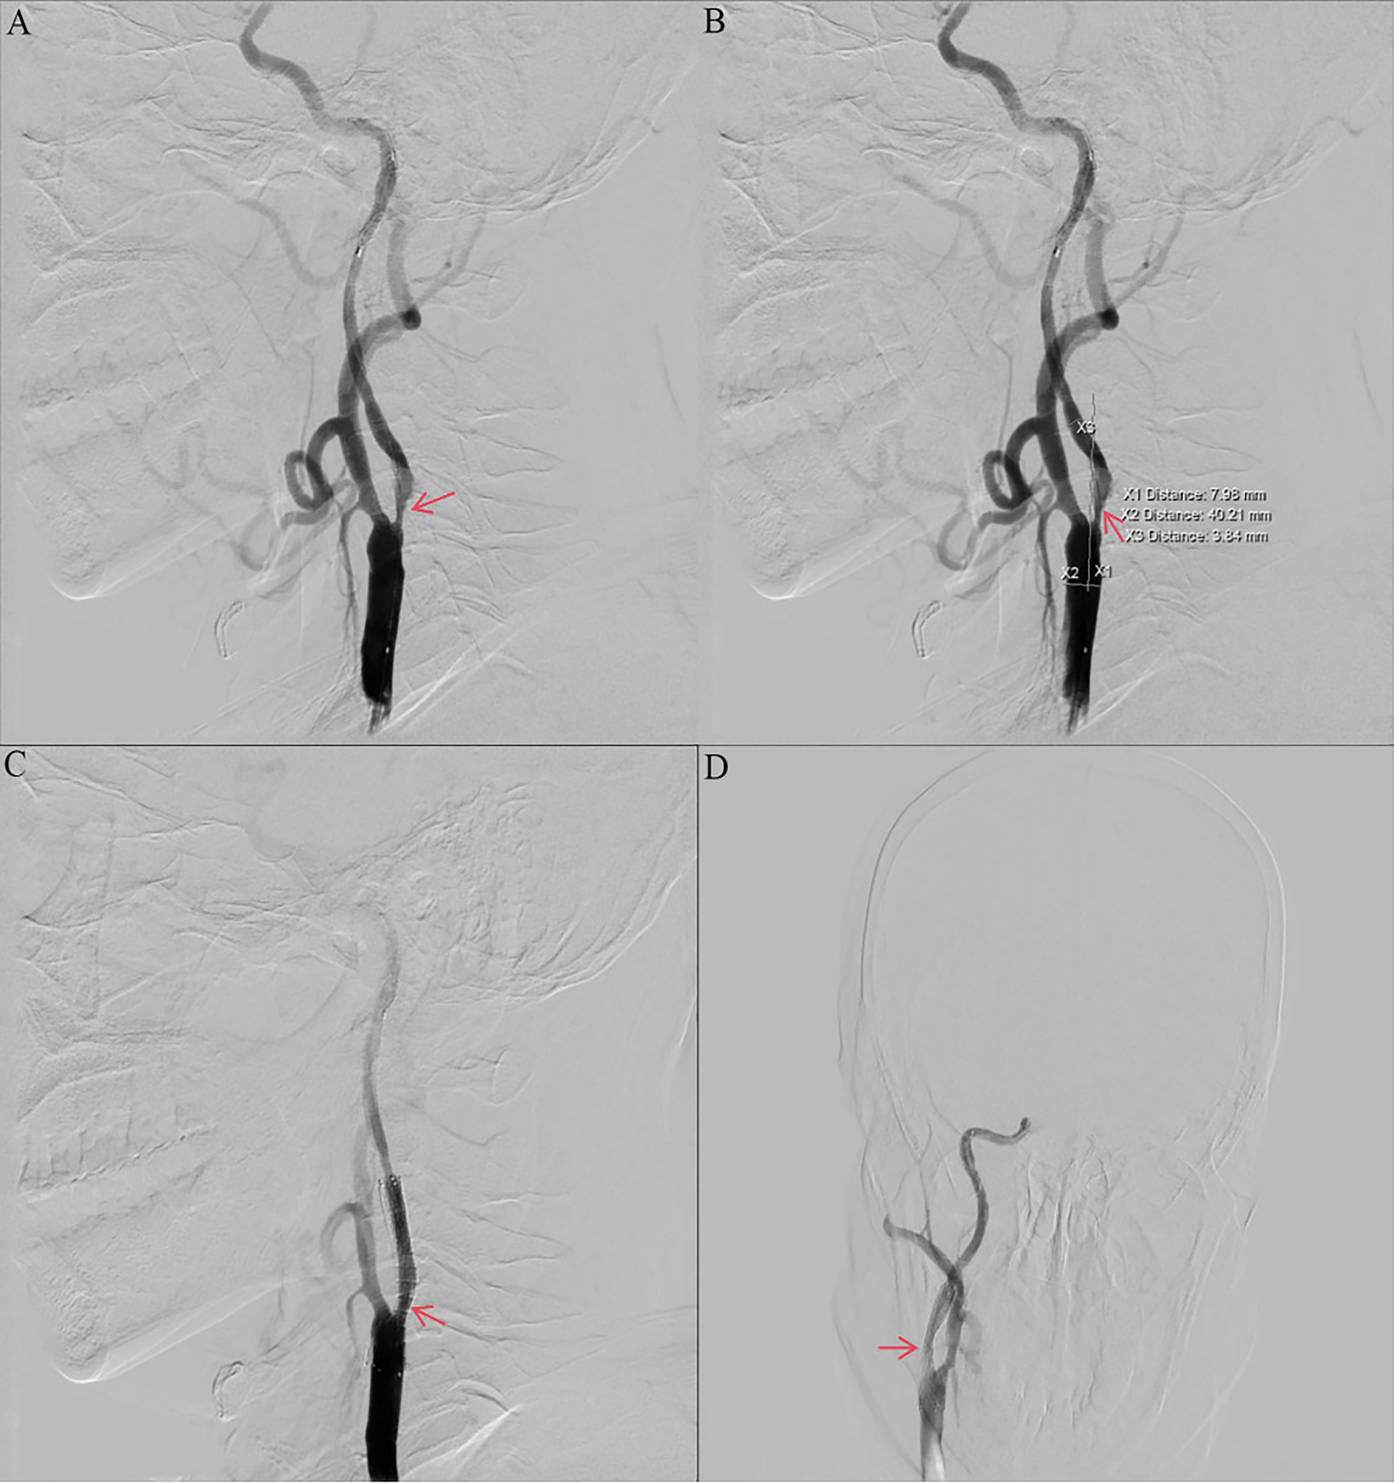

Other auxiliary investigations—including blood glucose, blood lipids, liver and renal function tests, coagulation profile, urinalysis, and thyroid antibody analysis—were unremarkable. Cardiac ultrasound and electrocardiogram findings were also normal. Vascular Surgery consultation recommended carotid endarterectomy (CEA) under general anesthesia. However, the patient and his family declined the procedure due to concerns regarding the risks associated with general anesthesia and the required neck incision. The patient decided to undergo internal carotid artery stenting under local anesthesia. Preoperative routine blood count (obtained two days prior to surgery) revealed a platelet count of 574 × 109/L. Intraoperative angiography demonstrated approximately 90% stenosis within the C1 segment of the right internal carotid artery (Figures 2A,B). The vessel diameter distal to the stenosis measured approximately 2.5 mm, while the common carotid artery diameter was approximately 7.9 mm. The stenosis was pre-dilated using a 4 mm × 30 mm LitePAC balloon inflated to 8 atmospheres(Atm). Subsequently, a 9 mm × 40 mm PROTEGE stent was successfully deployed across the stenotic segment. Post-procedural imaging showed improved antegrade flow with residual stenosis estimated at approximately 10%. Routine blood count on postoperative day 1 documented a platelet count of 415 × 109/L.

Figure 2

Preoperative and postoperative digital subtraction angiography. (a, b) Angiography of the right ICA before CAS showing stenosis with ulcers (NASCET 90% stenosis). (c, d) Angiography of the right ICA after CAS showing no residual stenosis and no thrombosis. ICA, internal carotid artery; CAS, carotid artery stenting; NASCET, North American Symptomatic Carotid Endarterectomy Trial; DSA, digital subtraction angiography.

The patient received dual antiplatelet therapy (aspirin and ticagrelor) and statin therapy. A stent was successfully implanted in his right internal carotid artery (Figures 2C,D). The CRUSADE scoring system was used to dynamically assess the risk of bleeding during hospitalization (in this case, the score was 24, which is low-risk), and hemoglobin alert values were set (immediate intervention for a drop of >2 g/dl). No recurrent cerebral infarction occurred. He was discharged on hospital day 19 with a modified Rankin Scale (mRS) score of 1. His discharge regimen included continued aspirin, ticagrelor, statin, and hydroxyurea. Discharge laboratory results showed a platelet count of 317 × 109/L (within normal range). Based on the platelet count trajectory and consultation with Hematology, the hydroxyurea dose was reduced to 500 mg/day. At the 1-month follow-up, his symptoms had significantly improved, with a platelet count of 471 × 109/L. Three-month follow-up included carotid ultrasound and platelet assessment (408 × 109/L). The ultrasound demonstrated a patent right carotid stent with smooth blood flow (velocity of 78 cm/s) and no evidence of restenosis. Following completion of 3 months of dual antiplatelet therapy (DAPT) and in accordance with ISTH Antithrombotic Guidelines for Myeloproliferative Neoplasms, ticagrelor was discontinued and antiplatelet therapy was transitioned to aspirin monotherapy. Throughout follow-up, the patient exhibited no progression to other hematologic complications associated with ET.